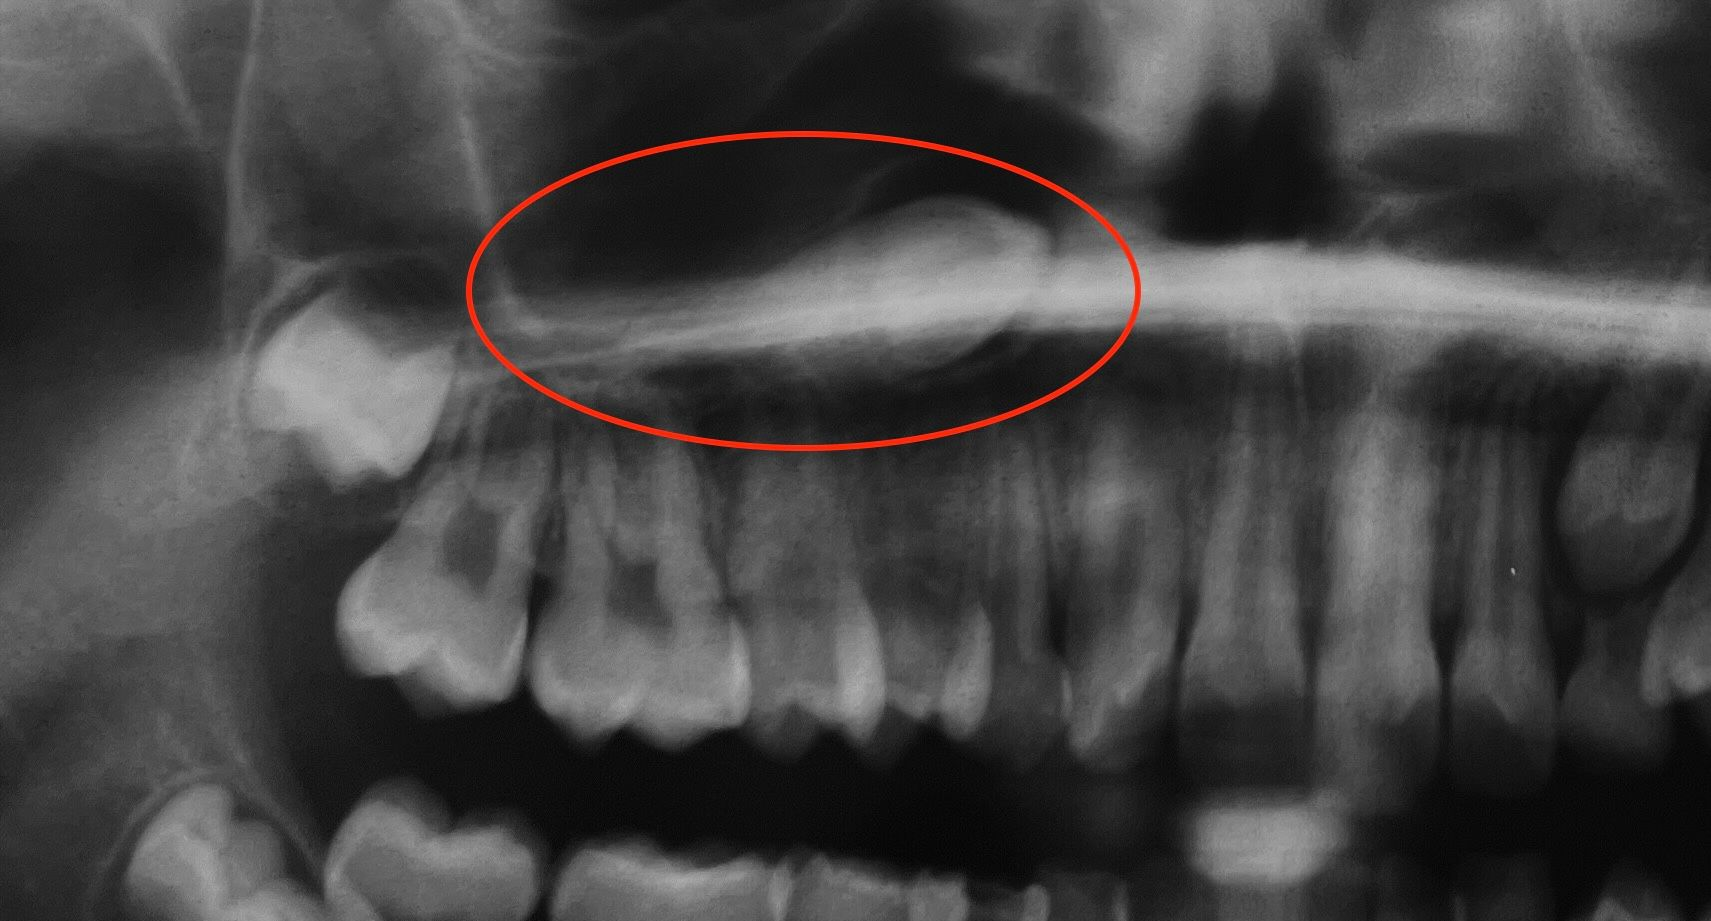

Rimozione di una cisti e agganciamento di un canino superiore incluso

Cisti che impedisce al canino di allinearsi

Rimozione della cisti e agganciamento del canino

Il canino viene trascinato nella posizione corretta

Il canino perfettamente allineato